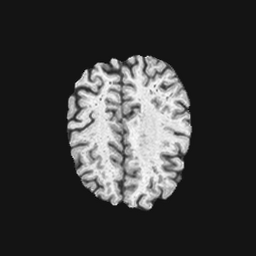

Exp. 1: Segmented adult brain data is used to evaluate our network’s regression performance with known ground truth Tisubscript𝑇𝑖T_{i}. 85 brains from the ADNI data set[1] were randomly selected; 70 brains for ΩtrainsubscriptΩ𝑡𝑟𝑎𝑖𝑛\Omega_{train} and 15 brains for ΩvalidationsubscriptΩ𝑣𝑎𝑙𝑖𝑑𝑎𝑡𝑖𝑜𝑛\Omega_{validation}. Fig. 2 shows an example slice of the ground truth and the reconstructed ΩΩ\Omega.

Figure 2: Example slice from the segmented adult brain MRI data set (a); reconstruction from 300 ωisubscript𝜔𝑖\omega_{i} based on SVRNet regression without SVR (b); SVR initialised with SVRNet predictions after eight iterations of SVR (c). Note that SVRNet (b) predicts individual slice transformations only from image intensities without any initial world co-ordinates of the sampled slice. (d) shows the achieved PSNR in dB when comparing the volumes of (b) and (c) to (a).

Reconstructing from Ti^^subscript𝑇𝑖\hat{T_{i}} initialisation without SVR yields a PSNR of 23.7 ±plus-or-minus\pm 1.09; with subsequent SVR the PSNR increases to 29.5±plus-or-minus\pm2.43 when tested on 15 randomly selected test volumes after four iterations of SVR.